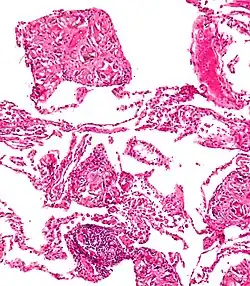

Surgical suture. H&E stain.

Splinters are common foreign bodies in skin. Staphylococcus aureus infection often causes boils to form around them.[11]